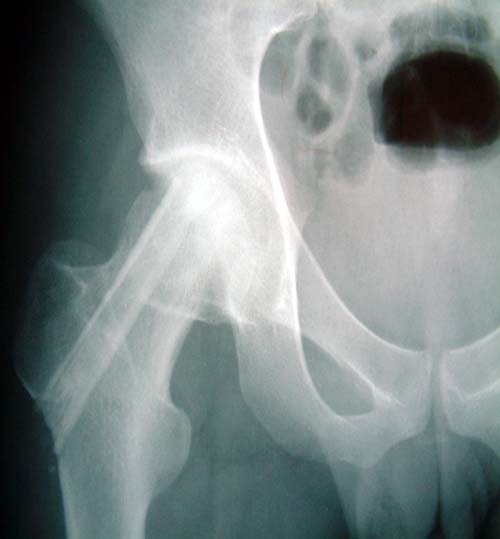

复合骨生长因子和自体骨髓干细胞的新型植骨材料植入支撑,恢复形态, 手术后24个月X线片,关节塌陷未加重,关节功能良好,无疼痛。